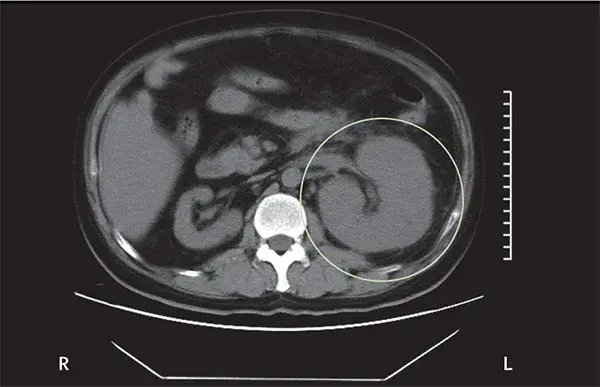

Um homem de 39 anos foi internado no hospital com história dia com dor no flanco esquerdo e tontura há um dia. Paciente tinha antecedentes de diabetes mal controlado e nefrolitíase obstrutiva à esquerda. Após avaliação inicial a TC do abdome mostrou aumento do tamanho do rim esquerdo devido gás no parênquima renal, espaço perirrenal e veia renal. Foi instituído tratamento com antibióticos e realizado de cirurgia aberta (elevado risco de embolização). O paciente evoluiu com melhora clínica e radiológica, TC de controle após 04 dias já mostrou redução do gás e do volume renal. Qual é o diagnóstico?

Caso típico de **pielonefrite enfisematosa** publicado no The Lancet ([link](https://www.thelancet.com/journals/lancet/article/PIIS0140-6736(19)30771-8/fulltext)). Os casos geralmente são decorrentes de infecção por _Escherichia coli_ em pacientes com diabetes descompensado e obstrução do trato urinário. A glicose é um substrato para proliferação de bactérias fermentadoras (_Enterobacteriaceae_), que produzem gás carbônico e hidrogênio. **Fica a dica do elevado risco de embolização**. Quando presente obstrução, a desobstrução da via urinária é mandatória. Nos casos com gás no parênquima ou espaço perirrenal, é sugerido fortemente drenagem percutânea, caso o gás fique limitado ao espaço coletor (pielite isolada) o manejo com antibióticos é suficiente.